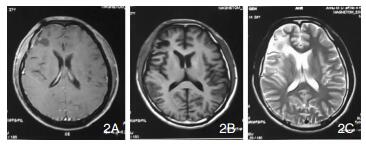

| 图 2 示第一次术后MRI |

|

| 图 5 示第三次术前MRI |

讨论:2007年WHO中枢神经系统肿瘤分类将颅内孤立性纤维瘤归为脑膜组织肿瘤中的间叶肿瘤[1],而2016年新分类将其单独划为间叶性非脑膜上皮性肿瘤[2],但国内外关于颅内孤立性纤维瘤多为个案报道,因此关于孤立性纤维瘤的诊治研究尚需进一步研究[3]。